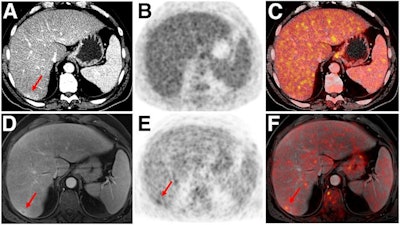

- Malignant bone disease (2.4%)

Indeterminate lesion on PET/CT classified by PET/MRI for 53-year-old man with lung cancer. Contrast-enhanced CT (A), PET (B), and fused F-18 FDG PET/CT (C) images are displayed in comparison with contrast-enhanced T1-weighted MRI (D), PET (E), and fused F-18 FDG PET/MRI (F) images. In CT (A), hyperdense, subcentimeter liver lesion (arrows) in segment VII is suggestive of transient hepatic attenuation difference or small hemangioma. As malignancy cannot be excluded, it needs further investigation. On PET/MRI, lesion is clearly classified as metastasis because of contrast enhancement and tracer uptake due to later acquisition time point. Follow-up CT confirmed diagnosis after 78 days. Image courtesy of the Journal of Nuclear Medicine.After exclusions, the researchers examined 1,003 PET/MRI scans of 918 patients. PET/MRI outperformed PET/CT in terms of providing more tumor information (26.3%), mostly in patients with malignant bone disease, followed by lung cancer, prostate cancer, and gynecologic or breast cancer. PET/MRI identified additional malignant findings in 5.3% of cases, which lead to a change in tumor, node, and metastases (TNM) staging in 2.9% of cases. PET/MRI also clearly classified indeterminate PET/CT lesions in 11% of cases.